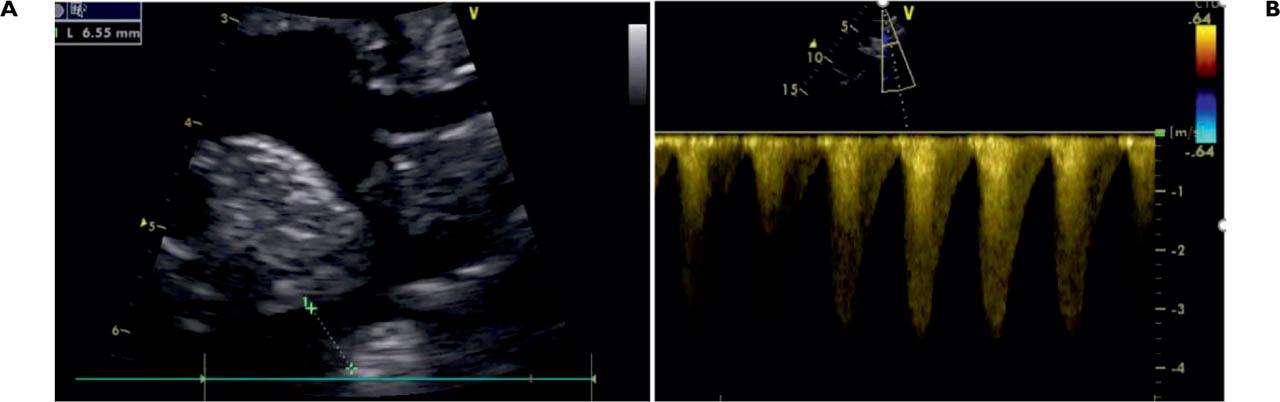

Figure 1